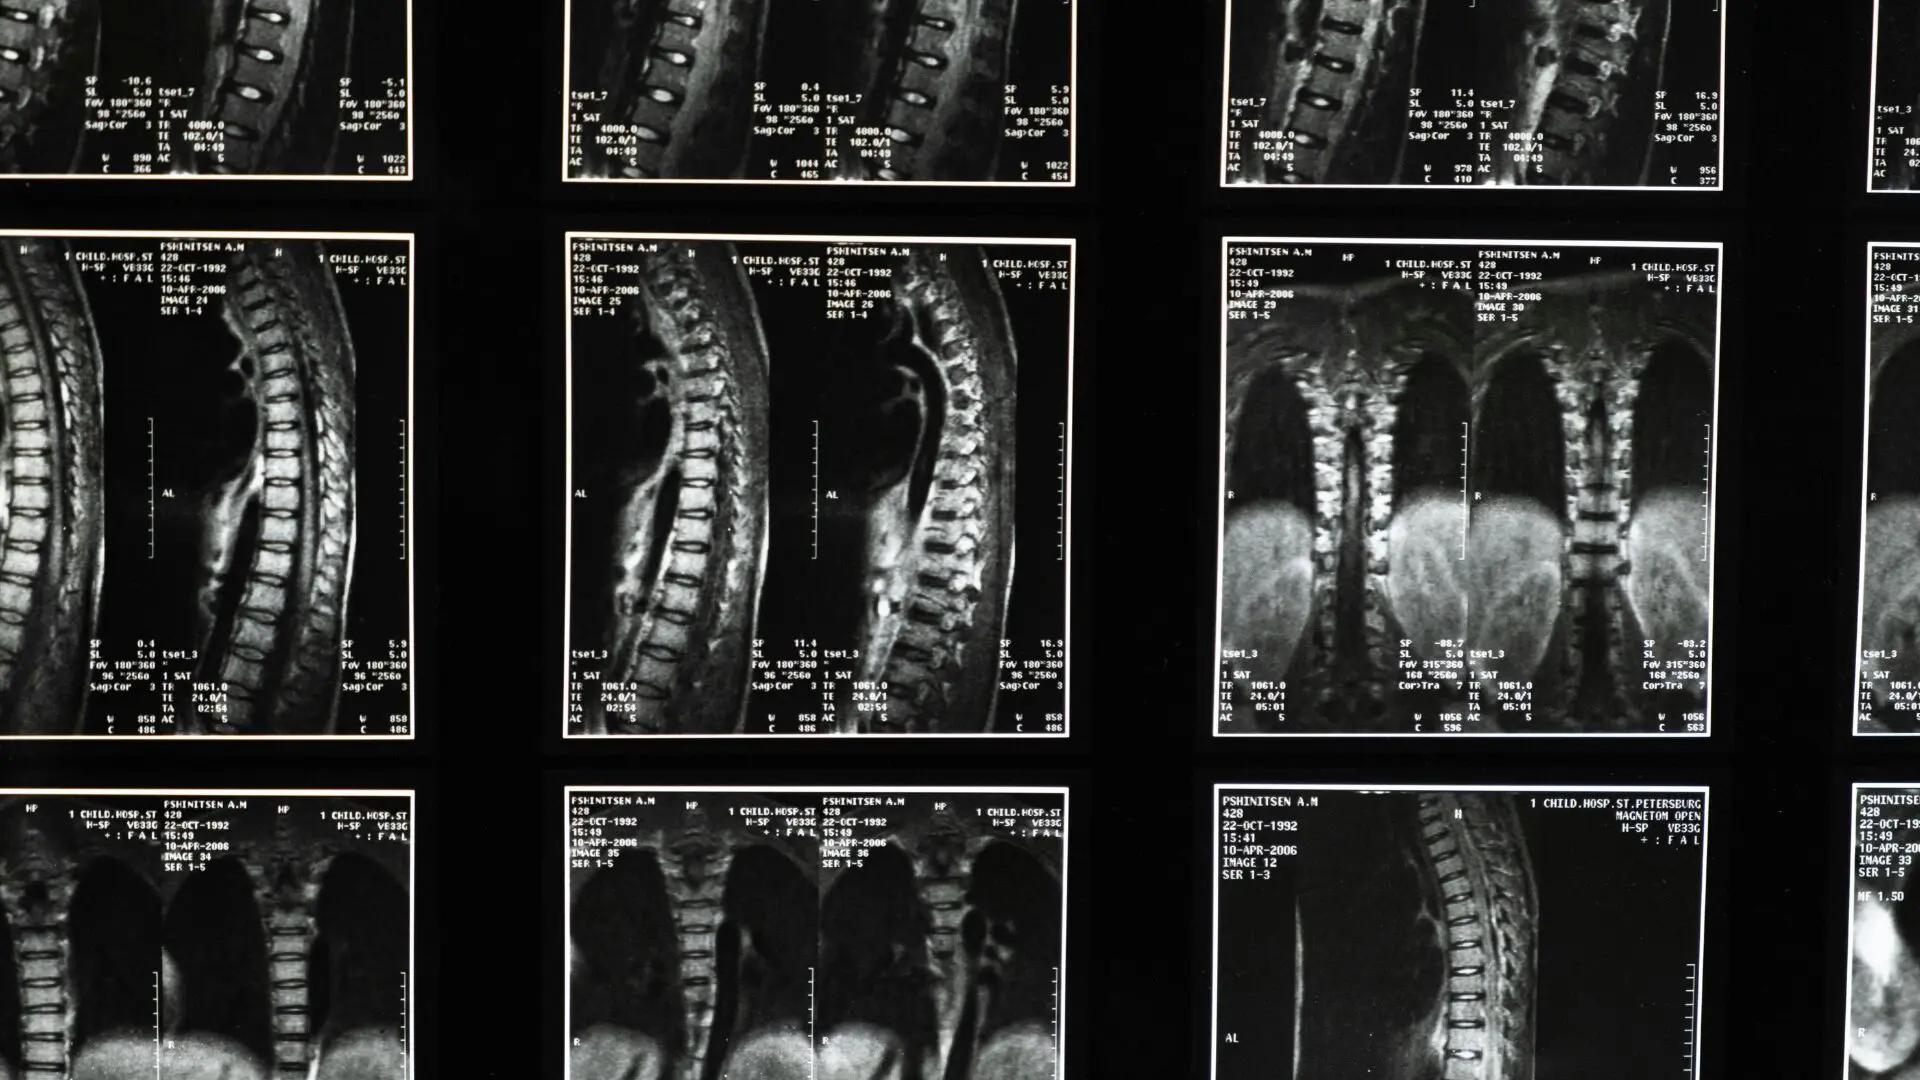

Mesmo com os avanços da medicina, atualmente, lesões na medula espinhal não podem ser totalmente curadas, e, portanto, o tratamento se concentra na estabilização do paciente, na prevenção de danos adicionais e na maximização da função.

O atendimento de emergência geralmente envolve a imobilização da coluna, a redução da inflamação e, por vezes, a realização de cirurgia para reparar fraturas ou aliviar demais pressões.

O procedimento da Universidade de Tel Aviv visa substituir a parte danificada por uma medula espinhal cultivada em laboratório que se funde com o tecido saudável acima e abaixo da lesão.